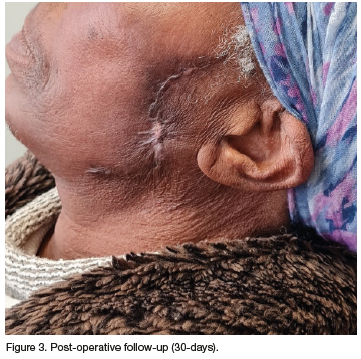

The lesion was excised under general anaesthesia with 10mm margins and closure of the defect was achieved with a bilateral Z-plasty. There were no peri-operative complications and patient had an uneventful recovery. On her 30-days follow-up, the wounds had healed uneventfully (Figure 3).